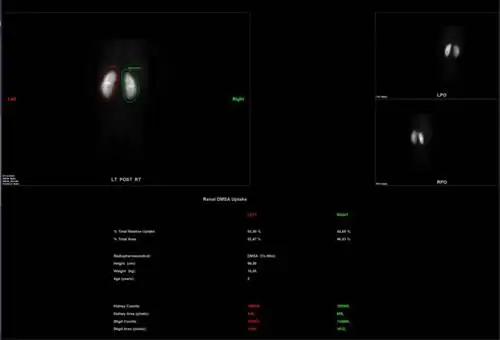

Почечная статика очень распространена даже у маленьких детей, перенесших инфекцию почек или мочевыводящих путей, например острый пиелонефрит. Это позволяет очень рано обнаружить так называемые функциональные поствоспалительные рубцы, которые могут регрессировать при правильном лечении. Нет другого неинвазивного метода, который сделал бы это возможным. Это также очень хороший тест при подозрении на врожденные дефекты почек, такие как: подковообразная почка, поликистоз почки, агенезия или гипоплазия почки, эктопическое положение почки.

Статика почек в норме, состояние после ОП